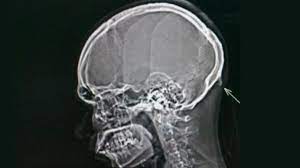

El hecho investigado ocurrió el pasado domingo en barrio Francini de Pichanal, cuando el acusado, luego de reclamar un supuesto robo al damnificado, le habría efectuado disparos con un arma de fuego, impactando uno de ellos en la zona del tórax, poniendo en riesgo su vida.